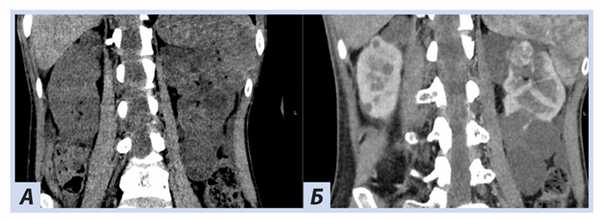

При скрининговом ультразвуковом исследовании забрюшинного пространства были выявлены изменения обеих почек, которые были интерпретированы как множественные кисты при дообследовании на КТ забрюшинного пространства: множественные кистозные образования обеих почек; в верхнем полюсе левой почки — кистозно-солидное образование, изоденсное паренхиме почки в нативную фазу (40 HU), в артериальную активно накапливающее контраст (до 100 HU), контуры его четкие неровные (рис. 5, 6).

Рис. 5. Пациентка П., 30 лет, с диагнозом «Болезнь Гиппеля−Линдау»: компьютерная томография забрюшинного пространства

Примечание. А — нативная фаза: кисты обеих почек, солидный узел в верхнем полюсе левой почки; Б — артериальная фаза: кисты обеих почек более отчетливы на фоне контрастированной почечной ткани, солидный узел в верхнем полюсе левой почки с неоднородным накоплением контраста опухолью.

Рис. 6. Пациентка П., 30 лет, с диагнозом «Болезнь Гиппеля−Линдау»: компьютерная томография забрюшинного пространства

Примечание. А — нативная фаза: кистозно-солидное образование левой почки; Б — артериальная фаза: кистозно-солидное образование левой почки с неоднородным накоплением контраста опухолью.